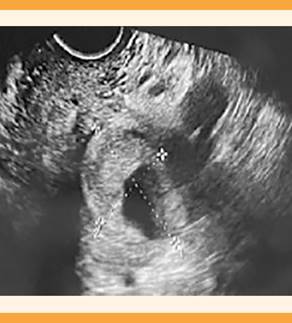

A los 35 días de la cesárea la paciente acudió al servicio de Urgencias debido a un sangrado de inicio súbito en cantidad mayor a la menstruación, con abundantes coágulos, hemodinámicamente estable en todo momento. Se decidió que la revisión se efectuara en el quirófano, previa infusión de un antibiótico y ácido tranexámico. Se advirtió que el cuello uterino tenía 1 cm de dilatación, con sangrado activo procedente de la cavidad uterina. Se practicó un legrado suave, guiado por ecografía, con la visualización del endometrio con imágenes de coágulos, pero no sugerentes de restos puerperales, y una imagen anecogénica redondeada en el segmento uterino, de 5 x 5 cm que impresionaba la malformación vascular con comunicación con la cavidad uterina (Figuras 1 y 2). Después del legrado y la infusión de antifibrinolíticos, la cantidad de sangrado disminuyó; se hospitalizó para control y ampliación del estudio. Una vez conseguida la estabilización de la paciente se repitió la ecografía con hallazgos similares y endometrio lineal. Ante la sospecha de patología vascular susceptible de abordaje mediante radiología intervencionista se trasladó a la paciente a un hospital de tercer nivel de atención.